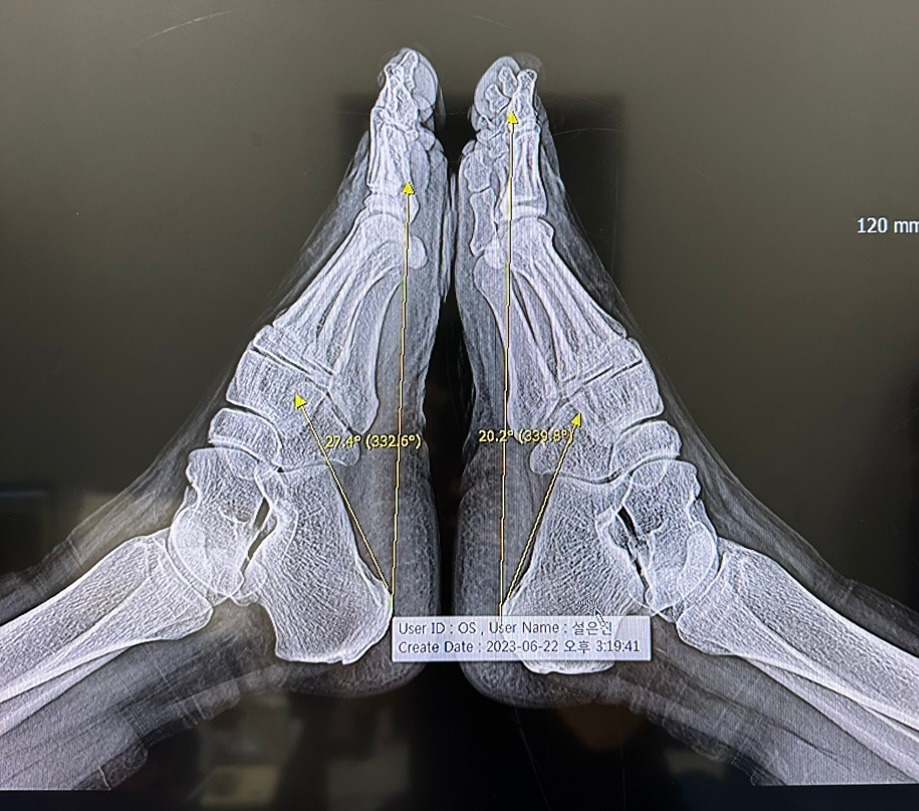

발 CT를 찍었는데, 그 당시 설명을 들으면서도 소재라고 생각해서 찍어두었다. 의사의 동의를 얻어 사진을 찍었다. 자세히 보면 왼발과 오른발의 각도가 달라졌는데 왼발은 27.4도, 오른발은 20.2도로 평평해졌다. 발이 평평해진 이유는 나이가 들수록 우리 몸의 근육이 빠지면서 이렇게 발이 평평해진다고 한다.